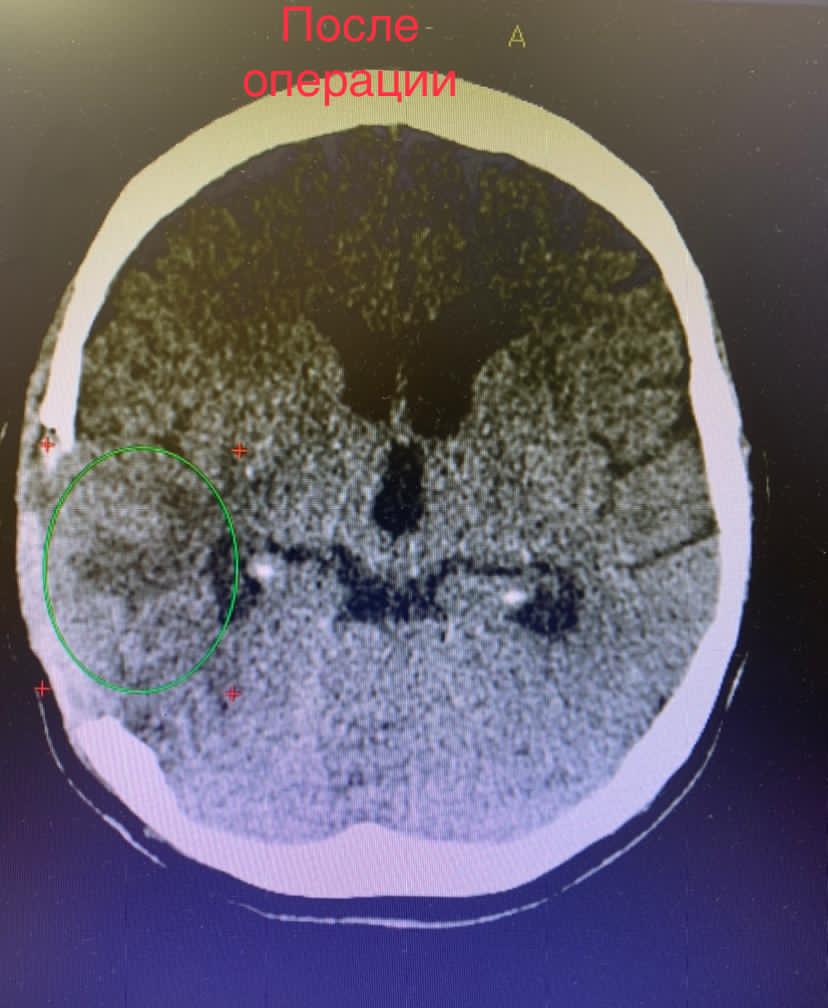

Выполнено микрохирургическое удаление опухоли единым блоком.

В послеоперационном периоде состояние пациентки оценивается как с положительной динамикой, уже на пятые сутки могла самостоятельно передвигаться.

Выписана в удовлетворительном состоянии на дальнейшее наблюдение к врачам- онкологам.